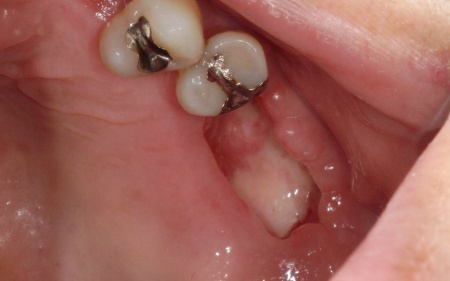

また、右下奥歯には、両隣の歯を土台にして橋を渡すように欠損部を補う被せ物「ブリッジ」が装着されていました。

右下奥歯は2本欠損しており、親知らず(第3大臼歯)と手前の奥歯(第2小臼歯)の2本でブリッジを支えていますが、これは親知らずに過度な負荷がかかる構造です。

親知らずはすでに大きく傾いており、こちらも温存が難しいため、ブリッジを除去してから親知らずを抜く必要があります。

次に、右下に装着されているブリッジを除去してから右下の親知らずを抜き、欠損部(第1大臼歯、第2大臼歯の部分)にインプラントを埋入しました。